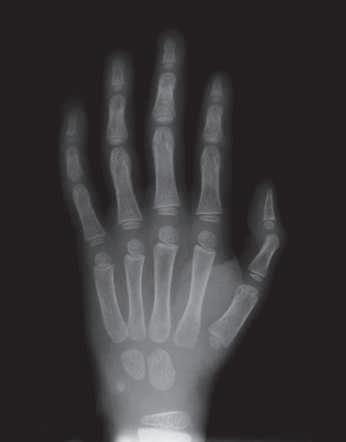

FIG. 1.11 • The presence of epiphyseal plates, as seen in a radiograph of a child’s hand, indicates that the bones are still growing in length.

separated by a thin plate of cartilage known as the epiphyseal plate, commonly referred to as a growth plate (Fig. 1.11). As skeletal maturity is reached, on a timetable that varies from bone to bone as detailed in Table 1.3, the plates are replaced by bone and are closed. To facilitate smooth, easy movement at joints, the epiphysis is covered by articular or hyaline cartilage, which provides a cushioning effect and reduces friction.